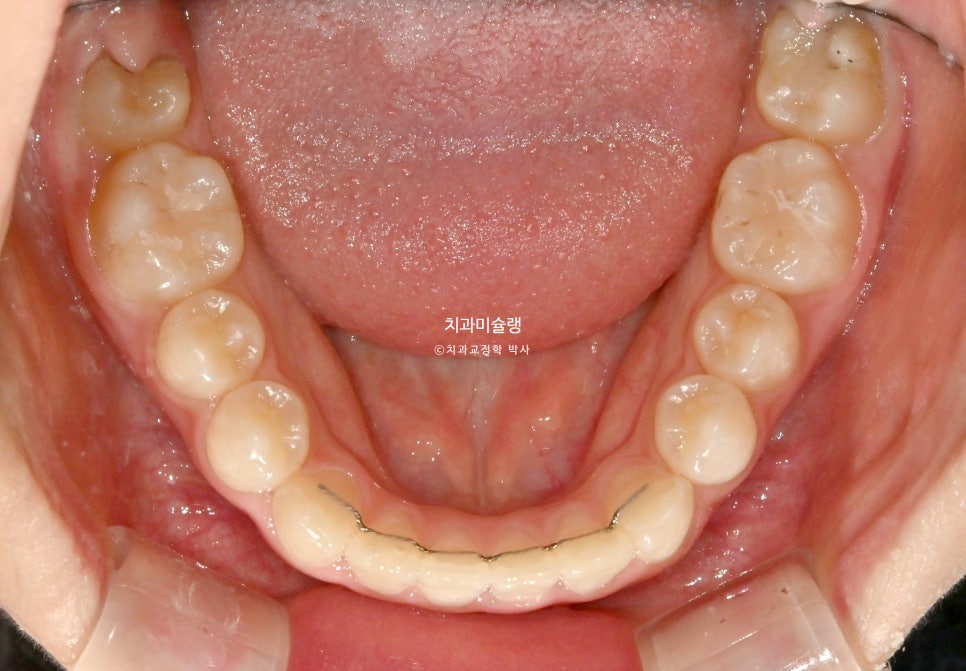

2026년 2월 – 치료 완료

2026년 2월, 정상교합이 달성되어 치료를 마무리 합니다.

중심선은 잘 맞으며 절단교합으로 인항 개방교합은 해소되었습니다.

어금니 교합관계는 1급을 달성.

3급 교합관계를 1급으로 만들기 위해 치료기간 내내 3급 고무줄을 사용했습니다.

결과가 성인교정치료 결과에 준한만큼 유지장치도 성인과 동일하게 들어갑니다.